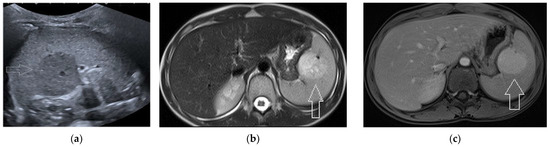

2.4. Cystic Lesions